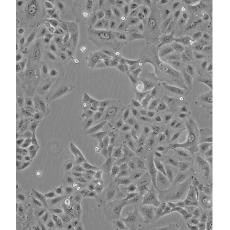

A549/DDP

中文名稱 人肺腺癌耐順鉑株

生長(zhǎng)特性 adherent

形態(tài)特征 epithelial